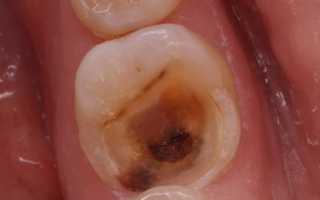

- Главная первопричина заболевания — запущенный кариес. При глубоком кариесе пульпа регулярно раздражается бактериями и токсинами. Истонченная эмаль позволяет постоянно раздражать пульпу. На нее влияют химические и температурные раздражители. Горячее, кислое, сладкое — все это травмирует пульпу.

Распознать пульпит можно в ходе инструментального осмотра у стоматолога. Врач выявляет кариозную полость с открытой пульпой. При касании к ней наблюдается резкая боль. Чтобы получить точные данные о характере и степени тяжести заболевания, необходимо пройти цифровую рентгендиагностику.